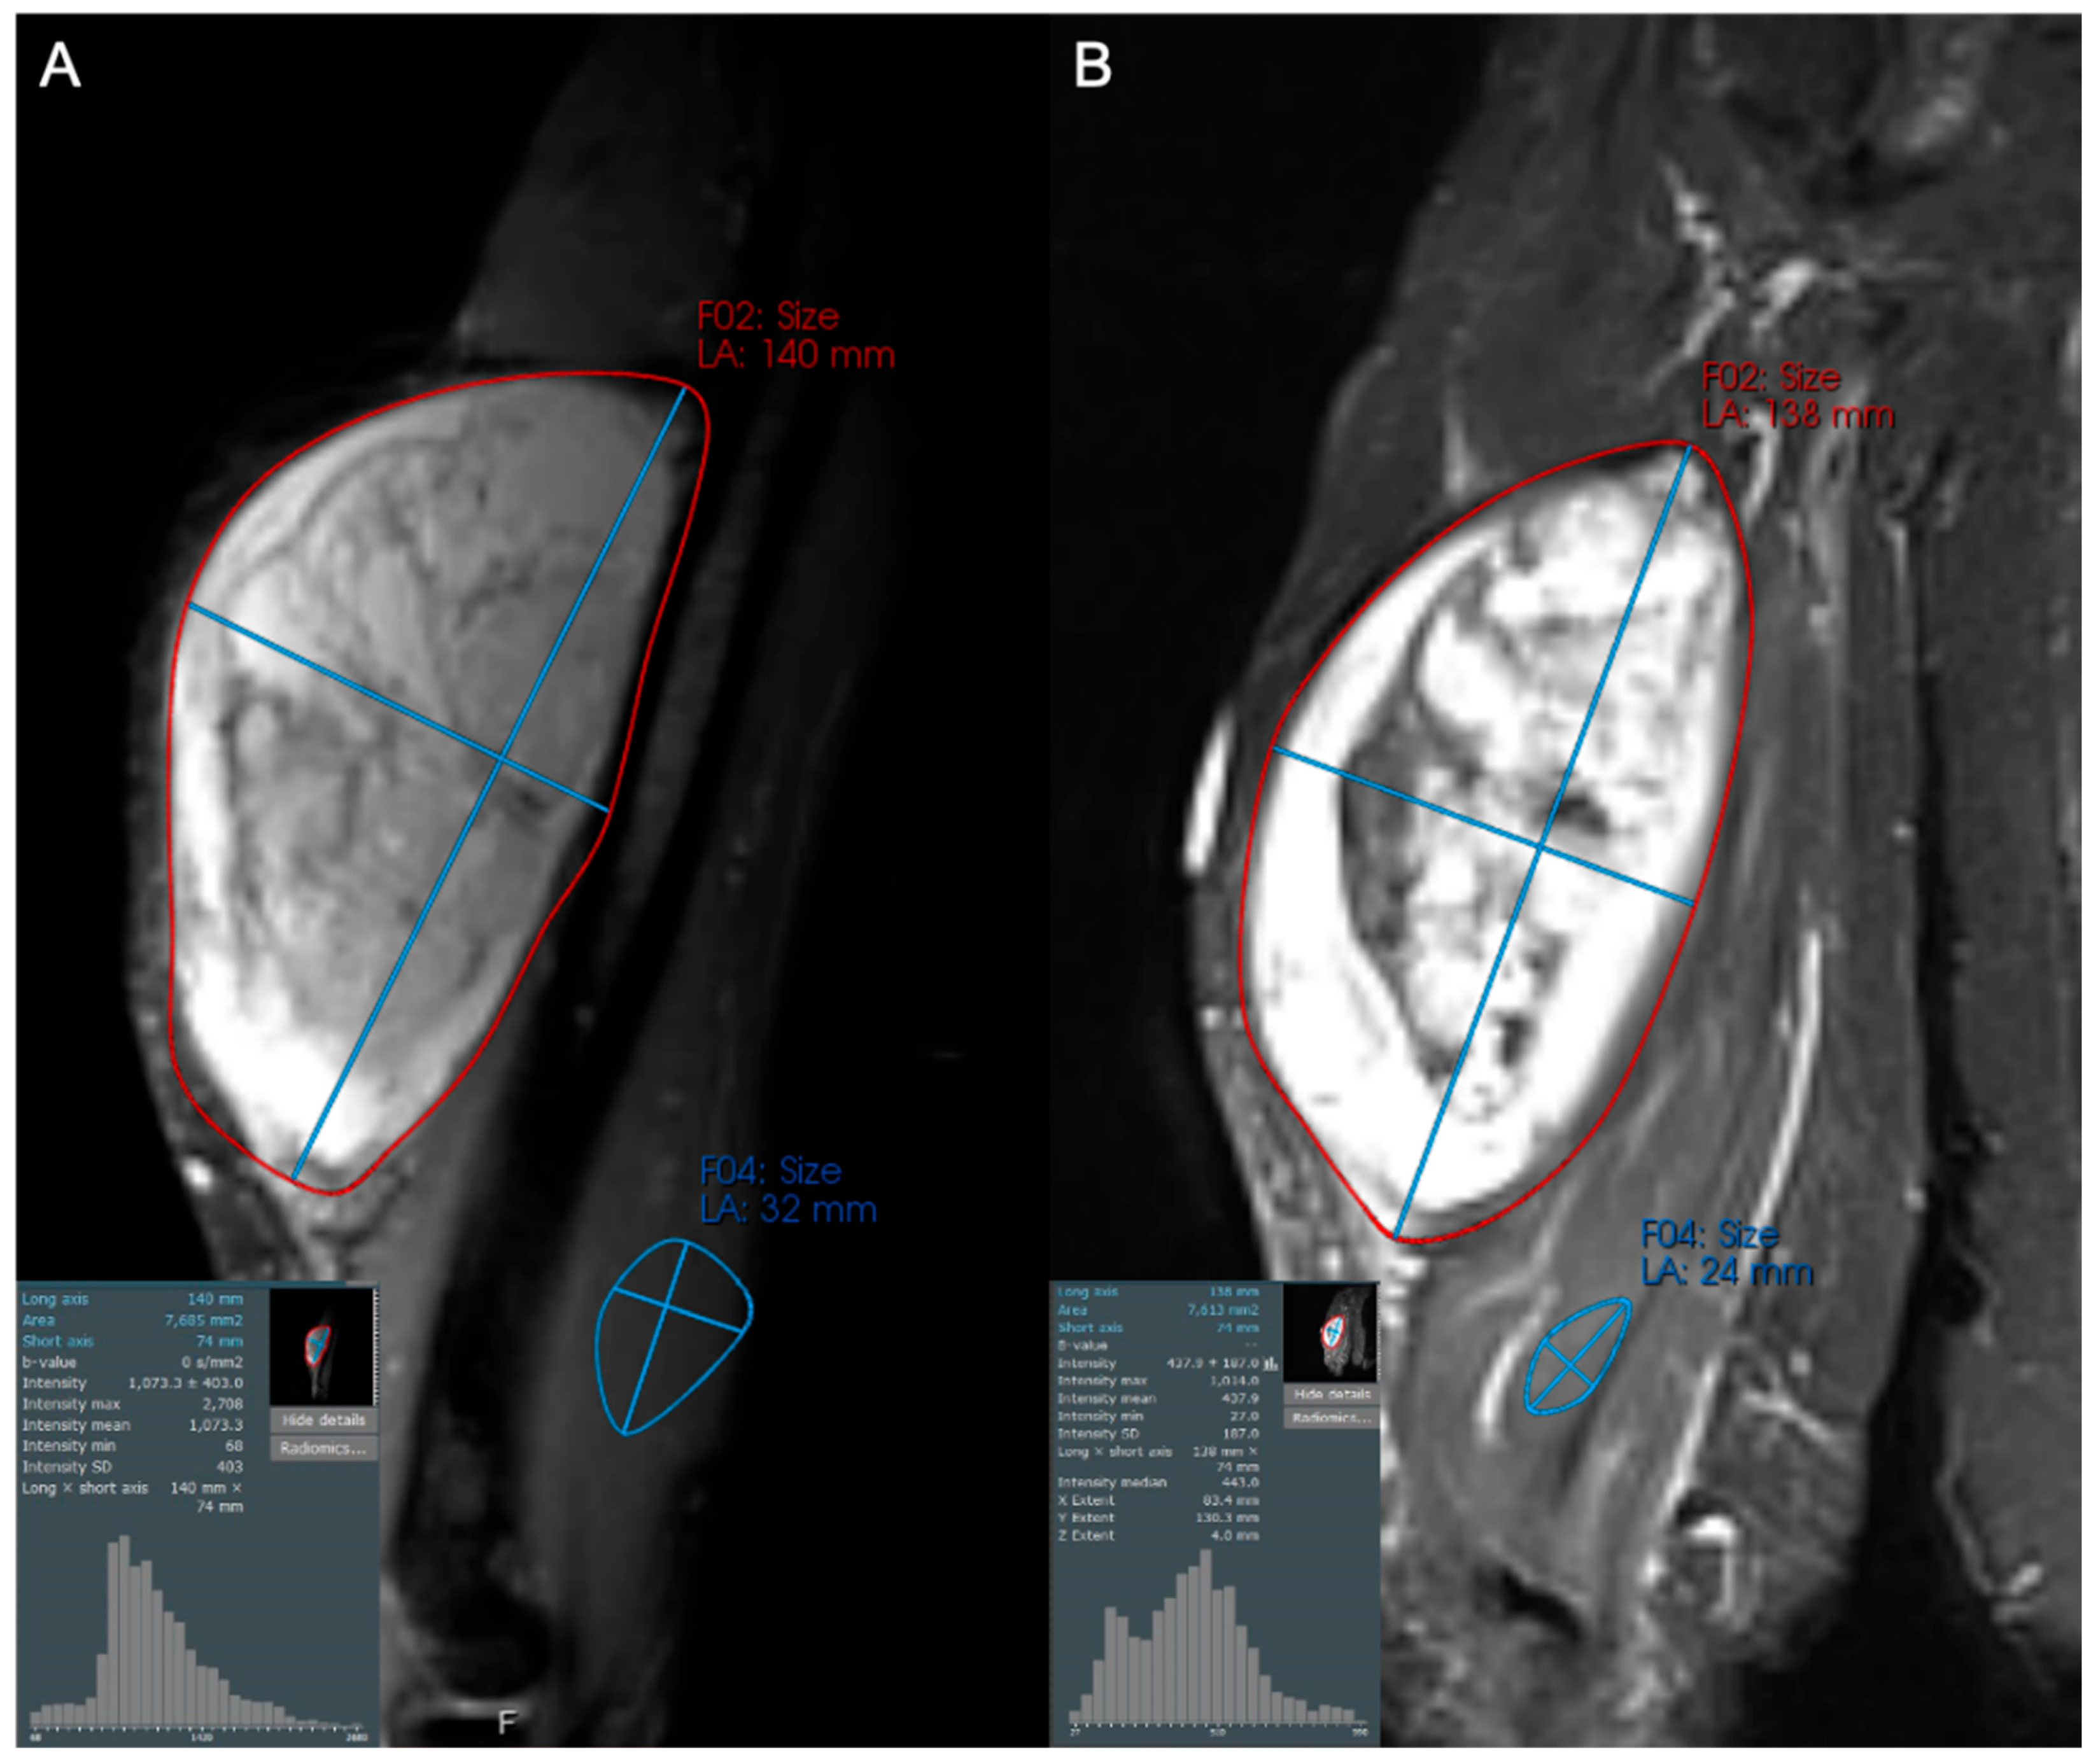

- Subhawong, T.K.; Feister, K.; Sweet, K.; Alperin, N.; Kwon, D.; Rosenberg, A.; Trent, J.; Wilky, B.A. MRI Volumetrics and Image Texture Analysis in Assessing Systemic Treatment Response in Extra-Abdominal Desmoid Fibromatosis. Radiol. Imaging Cancer 2021, 3, e210016. [Google Scholar] [CrossRef]

- Singer, A.D.; Pattany, P.M.; Fayad, L.M.; Tresley, J.; Subhawong, T.K. Volumetric segmentation of ADC maps and utility of standard deviation as measure of tumor heterogeneity in soft tissue tumors. Clin. Imaging 2016, 40, 386–391. [Google Scholar] [CrossRef]